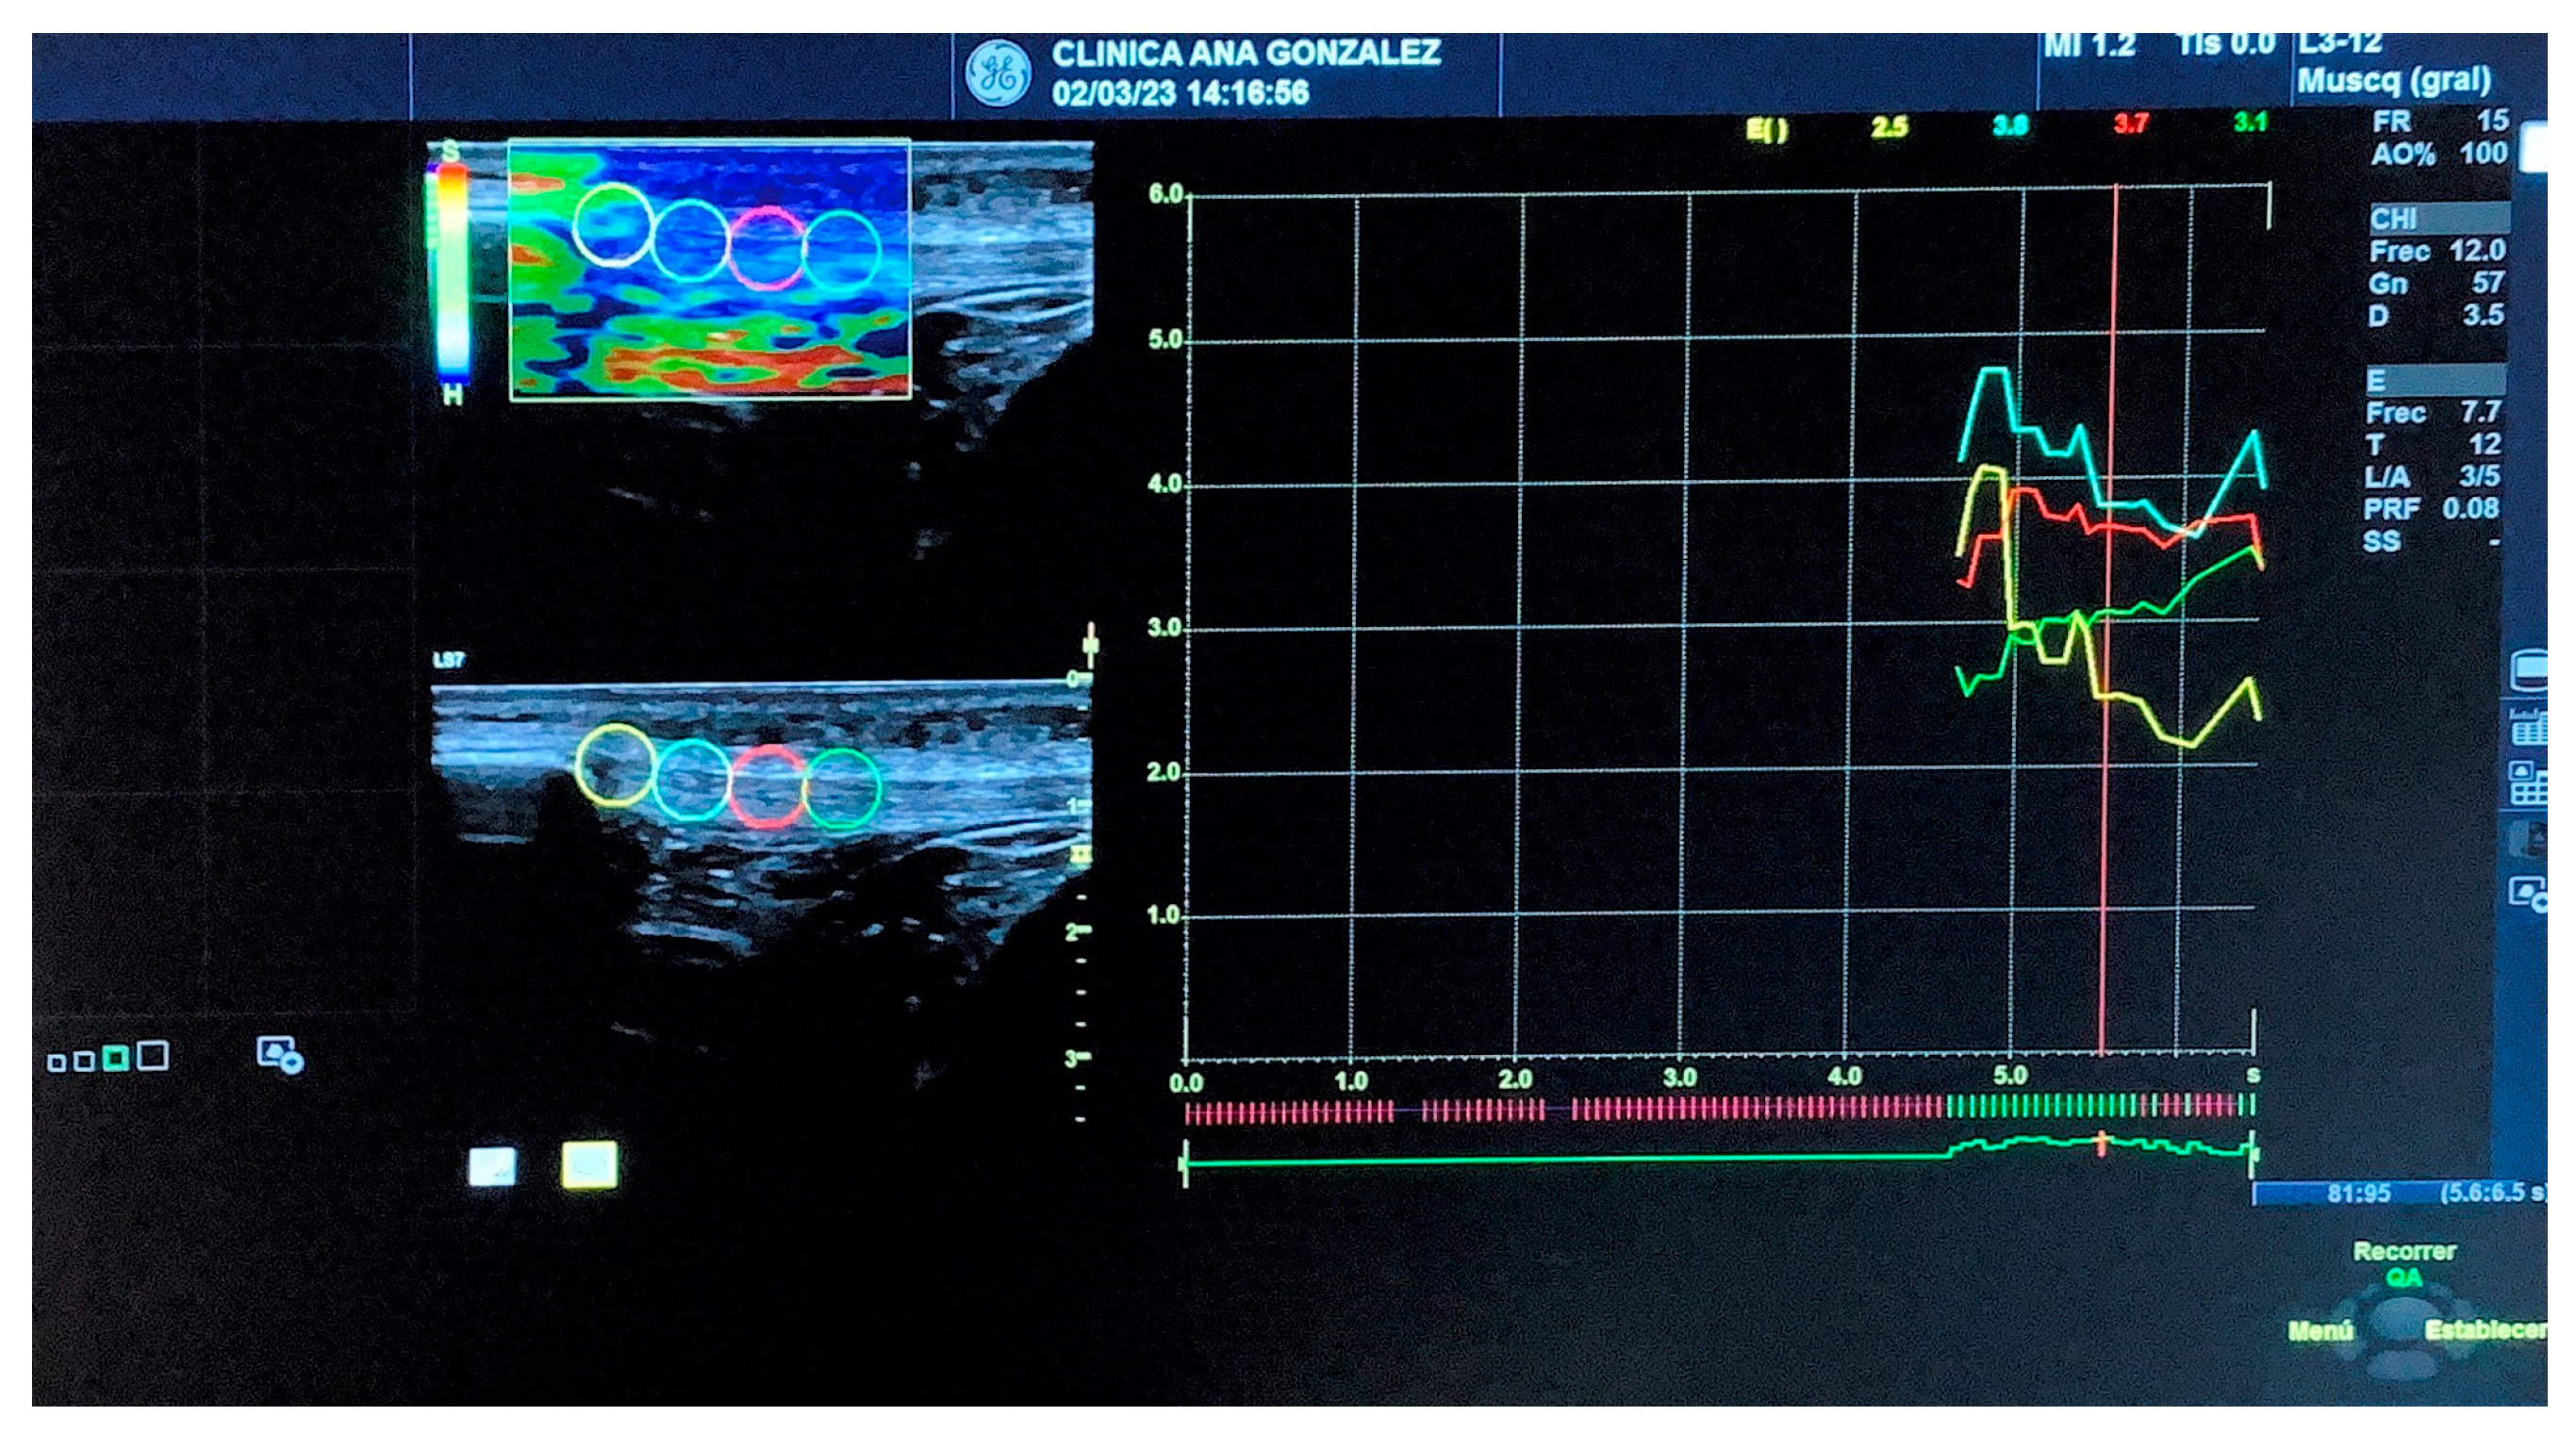

2.7.1. Strain Elastography